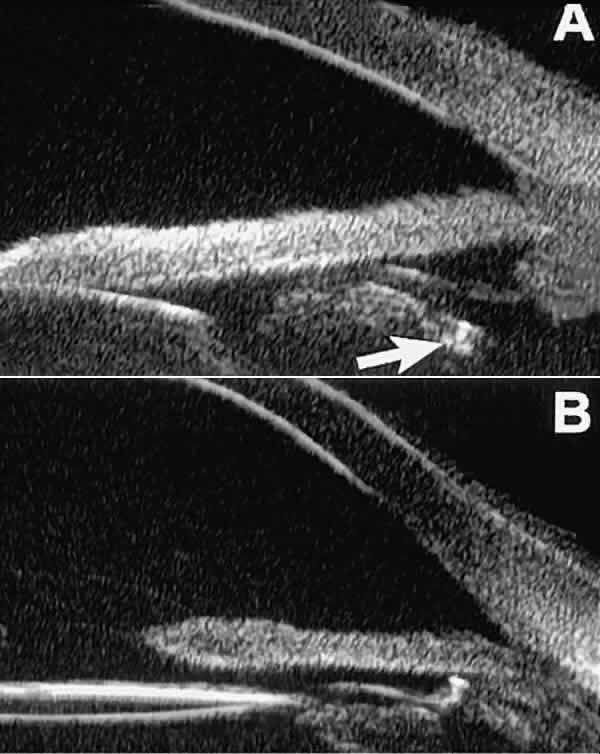

After blunt ocular trauma, UBM can be used to evaluate iris-angle abnormalities associated with and possibly obscured by hyphema, including angle recession and cyclodialysis, and to illustrate the presence and extent of blood clots.4 Angle recession is characterized on UBM (Fig. 21A) by posterior displacement of the point of attachment of the iris to the sclera. In the acute stage, the post-traumatic recess is usually filled with blood. Cyclodialysis (described and illustrated earlier) appears on radial UBM slices through the limbal region (see Fig. 13B) as a fluid-filled cleft between the sclera and ciliary body.13 This abnormality is by definition associated with at least a localized ciliochoroidal effusion.

Fig. 21. UBM features of ocular trauma. A. Angle recession with traumatic hyphema after blunt injury. B. Intracorneal foreign body (rose thorn fragment). Note inflammatory cells in adjacent aqueous. C. Intraocular foreign body (glass fragment in inferior angle).

After ocular perforations, lacerations, and intraocular surgery, UBM can show abnormalities such as retained foreign bodies too small to be imaged by other technologies.3,4 Foreign bodies appear on UBM (Fig. 22A and B) as highly reflective focal lesions that are frequently associated with inflammatory features.

Fig. 22. UBM features of primary neuroepithelial cysts of iris and ciliary body. A. Primary neuroepithelial cyst of iris midzone. B. Primary neuroepithelial cyst of iridociliary sulcus. C. Multiple neuroepithelial cysts of peripheral iris and ciliary body. D. Neuroepithelial cysts of pars plana of ciliary body shown in circumferential slice.